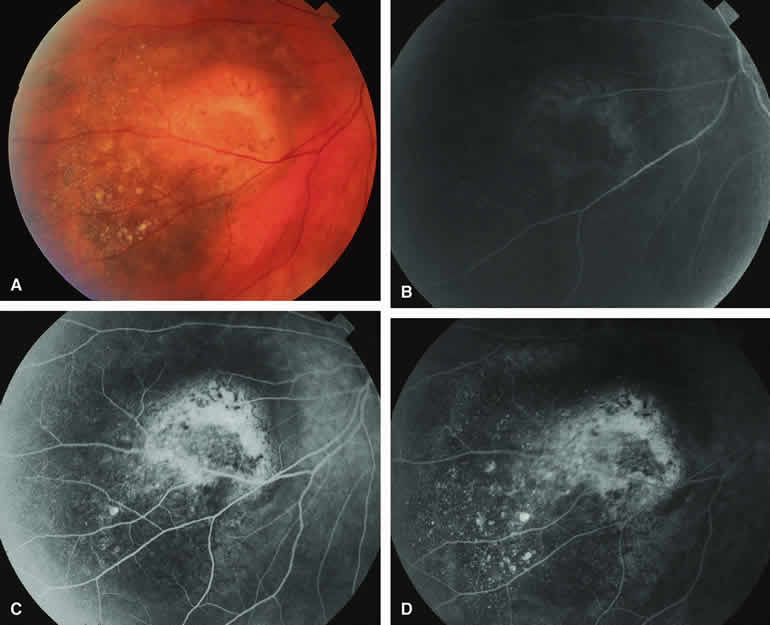

Typical Melanotic Choroidal Nevus

Fluorescein angiography of a typical choroidal nevus with bland surface features (see Fig. 1) shows the entire lesion to be hypofluorescent relative to the adjacent uninvolved choroid throughout the study. No large-caliber choroidal blood vessels are usually identifiable within the lesion. The retinal vasculature overlying the lesion appears well defined and normal on fluorescein angiography.

Choroidal Nevus with Drusen and Clumps of RPE Hyperplasia

If a choroidal nevus has drusen and RPE alterations on its surface (see Fig. 4A), fluorescein angiography (Fig. 4B, C, and D) tends to show patchy or stippled window defect hyperfluorescence corresponding to foci of RPE depigmentation, fluorescence blockage by clumps of RPE hyperplasia on the surface of the lesion, and late staining of at least some of the drusen. These features are not usually as evident on ICG angiography as they are on fluorescein angiography.